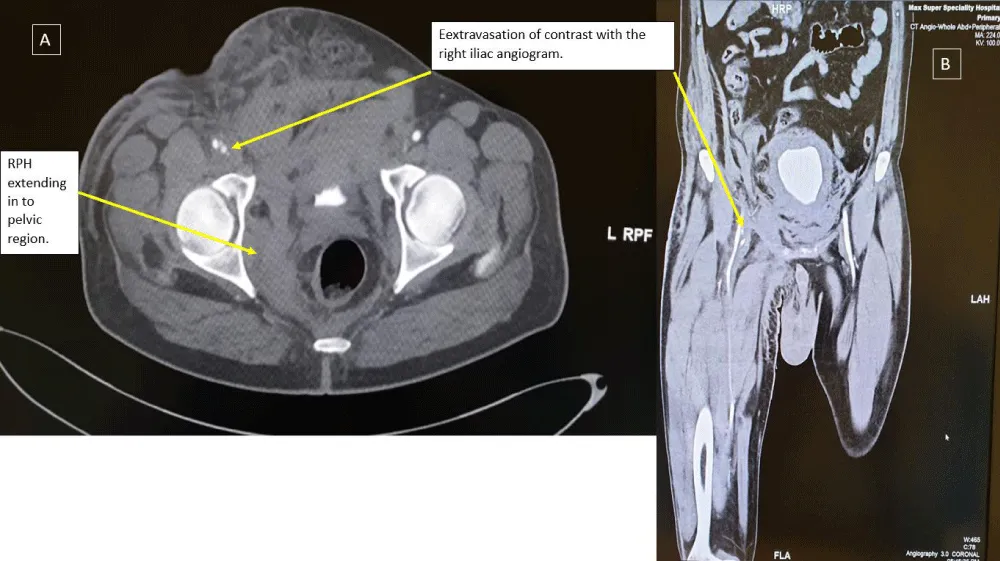

A 51-year-old male, nondiabetic with a history of angina on exertion and strongly positive exercise stress test for reversible myocardial ischemia with normal LV systolic function underwent left heart cardiac catheterization. He was found to have significant coronary artery disease (LAD/D1 true bifurcation lesion and significant stenosis in the proximal to mid circumflex artery. A 2.5 x 33 mm Xience stent (Abbott Vascular) was deployed in Left Circumflex artery. PCI to LAD/D1 true bifurcation was done with DK crush technique with a 3 x 38 mm Xience stent (Abbott Vascular) in LAD and 2.5x 18 mm Xience stent (Abbott Vascular) in D1 with good angiographic results. Aspirin and Ticagrelor were used as an antiplatelets. Intravenous antiplatelet were not given. Right common femoral arterial access was used which was a difficult puncture with three attempts. Right femoral venous access was also taken (single attempt). The patient was sent back to the coronary care unit with the instruction of removal of both femoral sheaths when activated clotting time (ACT) is less than 180 seconds and to be followed by manual compression and a tight pressure bandage to prevent hematoma. Thirty minutes after the procedure, the patient became hypotensive (systolic BP 70 mmHg) with bradycardia (heart rate: 36 beats/min) and treated as vasovagal syncope with atropine and Intravenous fluid. There was continuous blood oozing from sides of arterial sheath and from another arterial puncture site which was not responding to manual compression so both sheaths were removed in order to have more effective manual compression. Total one-hour manual compression given which led to no ooze in right groin even on coughing and then a compression bandage done. He have two more episodes of hypotension in next one hour in spite of rapid intravenous fluid transfusion. So inotropes with noradrenaline infusion was also initiated but blood pressure remained borderline. He was feeling fatigue and dizzy. Reinspection of right groin showed hemorrhagic bluish discoloration with scrotal swelling. The hemoglobin concentration fell from 15.1 (preprocedure Lab value) to 10.5 (ABG value) grams/deciliter. A CT angio scan of the abdomen and groin arteries showed a retroperitoneal and intraperitoneal hematoma with extravasation of contrast from right common femoral artery in to surrounding soft tissue suggestive of active leak of contrast, extending in the subcutaneous tissue in groin and lower right inguinal region (Figure 1). The patient was transferred back to the cardiac Cath lab because of persistent hypotension despite fluid resuscitation. Left common femoral arterial access was obtained and a 6 French sheath was introduced. A Judkins right (JR6) diagnostic catheter was passed retrogradely into the left common iliac artery and then antegradely into the right iliofemoral arterial system over a 0.035 inch guide wire. Digital subtraction angiography (DSA) showed the location of the retroperitoneal hematoma (RPH) (Figure 2).

Figure 1: Contrast computerized tomography of a retroperitoneal hemorrhage are shown in (A) coronal and (B) sagittal views. A large amount of extravascular contrast with the right iliac angiogram location near the middle third of the femoral head, suggestive of active bleeding from mid right common femoral artery into the pelvis.

Computed tomography (CT) study for these hematomas identifies four different anatomic locations relating to different routes of bleeding. These typical locations are retroperitoneal, intraperitoneal, groin and thigh and abdominal wall. The hematoma type so formed probably depends on whether the bleeding is confined to the femoral sheath and/or spreads into the femoral triangle as bleeding spreads along fascial planes [5].